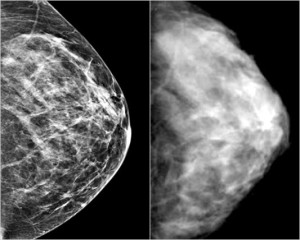

mammografia

La mammografia di routine per le donne dai 50 ai 70 anni ha ridotto del 50% nell’ultimo ventennio la mortalita’ per il tumore del seno. Ma ora e’ tempo di rivederne i criteri.